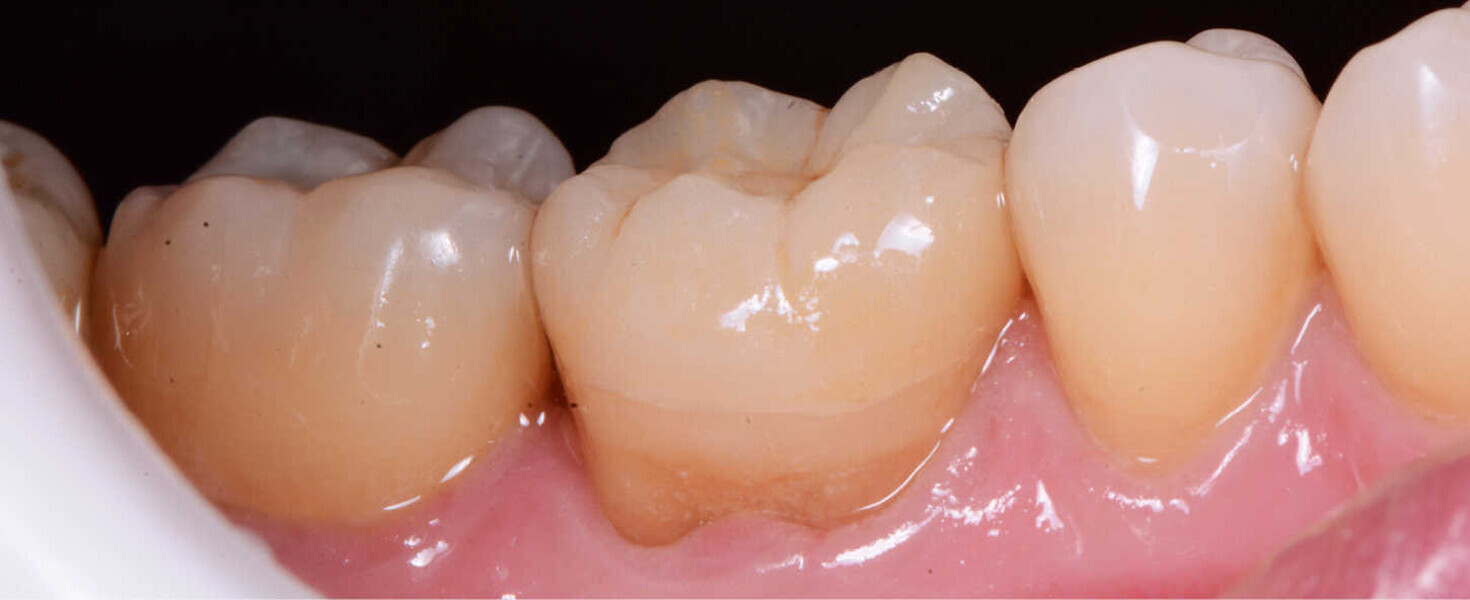

Figs. 12a y 12b. Vista final lateral y oclusal.